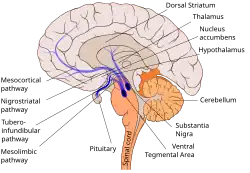

The tuberoinfundibular pathway refers to a population of dopamine neurons that project from the arcuate nucleus (a.k.a. the "infundibular nucleus") in the tuberal region of the hypothalamus to the median eminence.[1] It is one of the four major dopamine pathways in the brain. Dopamine released at this site inhibits the secretion of prolactin from anterior pituitary gland lactotrophs by binding to dopamine receptor D2.

Some antipsychotic drugs block dopamine in the tuberoinfundibular pathway, which can cause an increase in the amount of prolactin in the blood (hyperprolactinemia).

Relationship of the hypothalamus and the pituitary gland. The anterior pituitary, or adenohypophysis, receives rich blood flow from the capillaries of the portal hypophyseal system. This system delivers factors released by hypothalamic neurons into portal capillaries at the median eminence. The figure shows one such projection, from the tuberal (arcuate) nuclei via the tuberoinfundibular tract to the median eminence.